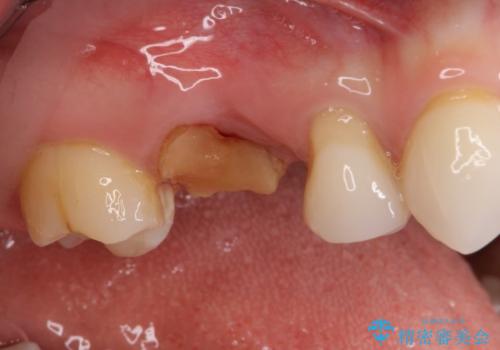

- 近医で奥歯の抜歯が必要であると指摘され、インプラント治療を希望して来院された患者様です。

診察の結果、大きな虫歯となっている歯は抜歯が望ましく、抜歯後にストローマンSLActiveを埋入することとしました。